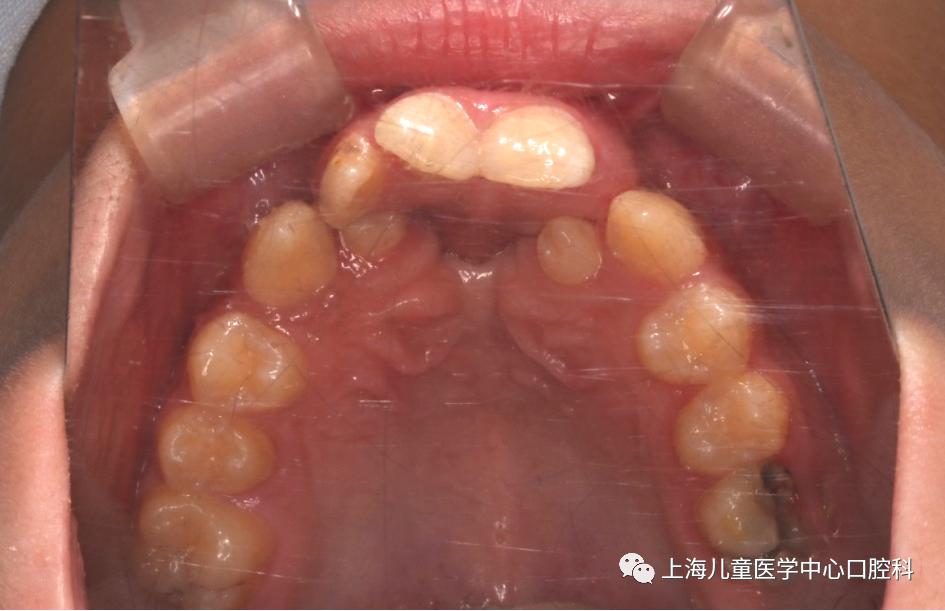

唇腭裂是一种较为常见的口腔和面部先天发育畸形,在我国,每一千人中就有一人可能患有唇腭裂,每年有数以万计的唇腭裂新生儿问世。唇腭裂对患儿的口腔形态和功能,例如发音,咀嚼和吞咽等均会造成影响。今天来和大家分享关于唇腭裂正畸治疗你需要知道的事儿。01

1. 牙齿排列:唇腭裂患儿常发生牙列不齐、牙列拥挤等错颌畸形,且常伴有先天性缺牙,牙齿形态异常;

2. 乳牙期和替牙期:唇腭裂患儿早期即可出现错颌畸形如前牙反合(俗称“地包天”),上颌骨牙弓狭窄,牙齿异位萌出等,及时矫正妨碍颌面正常生长发育的错颌畸形有利于患儿的生长发育;